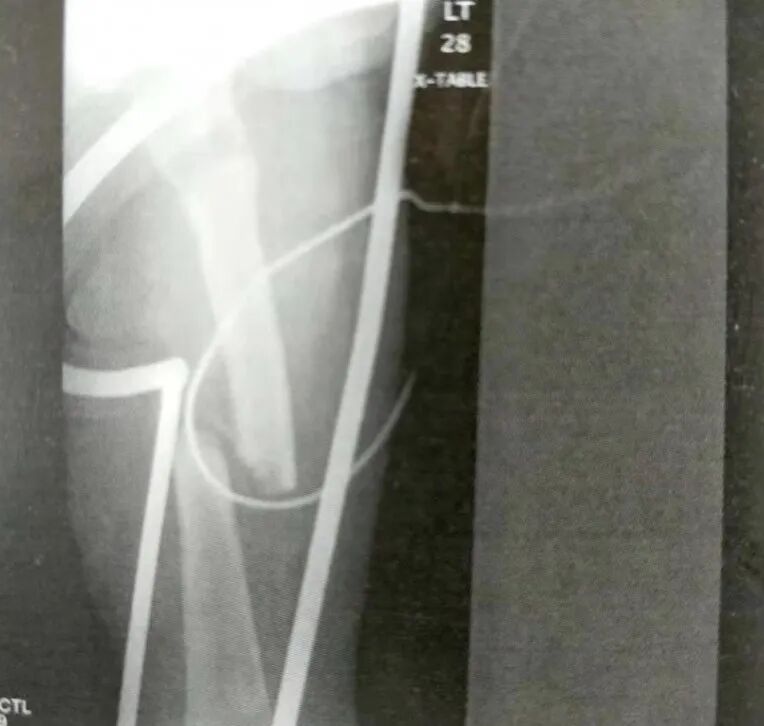

4)简单骨折进行绝对稳定固定时,金属板的工作长度可以短。然而,当使用桥接接骨板进行相对稳定固定时,金属板的工作长度必须仔细考虑。

• 对简单骨折进行相对稳定固定时,金属板的工作长度必须较长以避免应力集中。最好在骨折位置留三四个孔空着(在转子下骨折线上的骨折近端至少需要两枚螺钉)。

• 对粉碎性骨折进行相对稳定固定时,桥接接骨板技术可以获得长的工作长度。不要试图在骨折块之间进行固定,因为不可能达到绝对稳定固定和解剖复位,反而会导致应力集中。

▲ 示意图

5)金属板的长度应该两倍于工作长度(只受股骨长度的限制)。如果采用桥接接骨板进行相对稳定固定,接骨板的螺钉孔数很少少于10个。

▲ 金属板的长度应两倍于工作长度

6)如果术前计划对转子下骨折进行绝对稳定固定,就需要拉力螺钉结合加压接骨板或者中和接骨板。目标是在骨折两端各有8~10个皮质的固定。达到绝对稳定时就没有工作长度的概念,并且可以使用短一些的金属板。